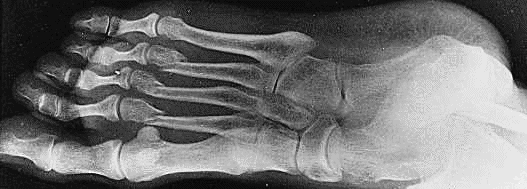

Jeste li se ikada ozlijedili? Tada su vam pomogle roengentske ili

x-zrake.